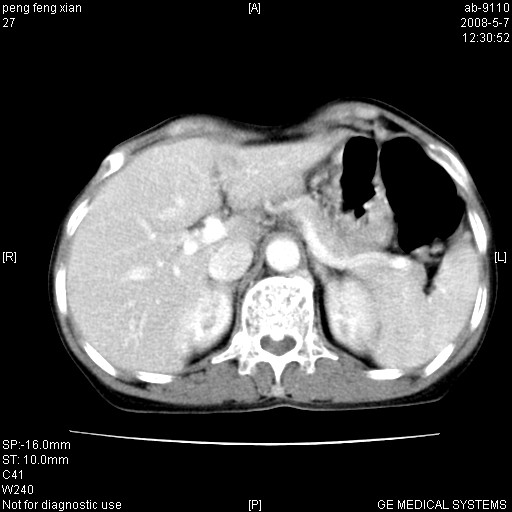

女,56岁。b超左一腹包块,考虑胃肠道肿瘤。

胃壁增厚,左前胸壁局限性隆起,考虑胃癌可能性大,建议做胃镜

典型胃癌胰体尾部受侵。

胃体部胃壁增厚,不均匀性强化,与胰腺分解欠情.

考虑:胃癌,胰腺受侵待除外.

鉴别:胃淋巴瘤(强化不明显)

建议:胃镜检查.